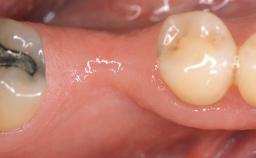

GBR and Soft-Tissue Augmentation Following Explantation to Rehabilitate a Soft- and Hard-Tissue Defect

It is sometimes necessary to remove and replace compromised implants. This case is a clear example of the need for multiple steps to achieve an optimal therapeutic result for patients with non-salvageable implants. It illustrates how the lost soft and hard tissues were rebuilt in a sequence that improved the healing of the hard tissues and assured their long-term stability. The 35-year-old healthy patient presented with clinical attachment loss on the proximal and lingual surfaces of the natural dentition. Some gingival recession was present on natural teeth, particularly in the posterior sextants (S1, S3, S4, and S6).